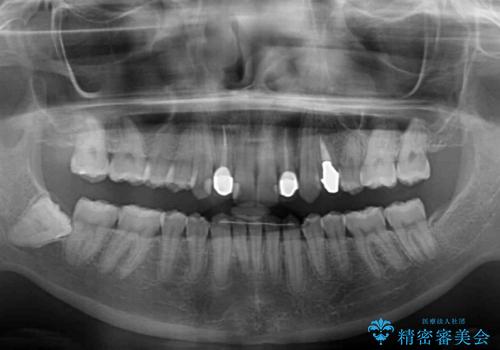

- 前歯の歯並びと神経を取って変色してしまった前歯を気にして来院された患者様です。

上下前歯の歯列不正はインビザラインにより整え、その後に、前歯2本をオールセラミッククラウンにて補綴治療することとしました。

下顎前歯が1本欠損しており、下顎歯列の大きさが本来よりも小さいため、上顎歯列とのバランスが悪く、深い咬み合わせになっていました。

上顎にIPRを多用して歯列の大きさを小さくするよう試みましたが、理想的な咬み合わせまでには改善させることはできませんでした。